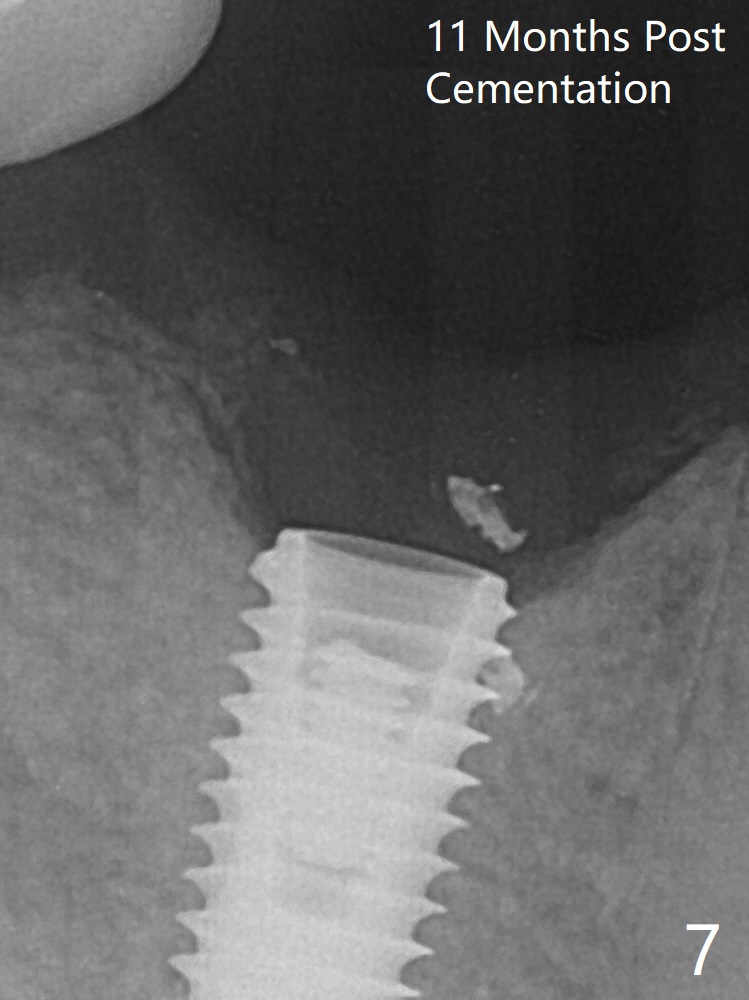

When the residual roots of the tooth #30 (Fig.1) are removed, the buccal crest is found ~ 2 mm apical to the lingual one (Fig.2 <); while the initial depth of osteotomy is 11.5 mm (yellow lines), the parallel pin is 10 mm long.  To place a 5x11.5 mm implant at the level of the buccal crest (Fig.4 (>45 Ncm)), subsequent osteotomy depth is 13 mm using the lingual crest as a landmark (Fig.3 (4 mm drill in place)).  After insertion of a 5.7x5.5(3) mm abutment, Vanilla Graft is placed (Fig.5 * with 2 mm buccal gap).  The abutment with a provisional is loose 4 months postop (Fig.6).   The permanent restoration is cemented 6 months postop.  The abutment screw is loose and fractured 8 and 11 months post cementation, respectively (Fig.7).  The fractured screw seems to be loose within the implant well and is easily re-winded out using Screw Removal Kit (sr-kit.html).  When the crown/abutment at #30 is loose 2nd time 1 year 7 months post cementation (Fig.8 taken post retightening), the screw at #19 fractures.  The tooth #2 needs a crown.  The patient cannot use the anterior teeth, since the teeth #8 and 9 have root fracture.  Can extraction and bone graft increase bone height?  The screw re-fractures 9 months later (Fig.9).  The dislodged crown is sectioned; the abutment is reseated completely (Fig.10) for a new crown. The tooth #2 needs RCT, B-U and crown, while the tooth #1 extraction (Fig.11).